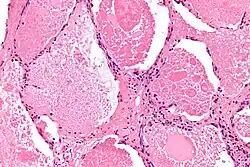

In PAP, surfactant proteins and lipids accumulate in the alveoli, impairing gas exchange and leading to respiratory insufficiency. WLL works by instilling large volumes of saline into the lung, which helps to dissolve and mobilize these accumulated materials. The saline, along with the dissolved surfactant, is then drained from the lung, effectively clearing the alveolar spaces.[13]

Restoration of alveolar function

By physically washing out the debris and excess surfactant, WLL restores the normal architecture of the alveoli. This improves their ability to facilitate gas exchange, leading to better oxygenation of the blood and overall respiratory function.[14]